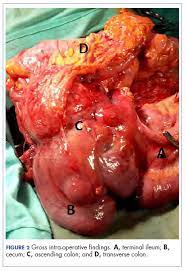

Many of the early signs and symptoms of cancer in children can also be caused by common illnesses or injuries, making childhood cancer hard to recognise and difficult to diagnose. Signs and symptoms of childhood colorectal cancer usually depend on where the tumor forms. Intestinal obstruction is a blockage that keeps food or liquid from passing through your small intestine or large intestine (colon). The tests are the only way to spot early cancer. Symptoms signs and symptoms of colon cancer include:

Cancer can also occur in the small bowel, but this is unusual. However, these symptoms are very common and most people with them do not have bowel cancer. Or strictures from an inflamed intestine caused by certain conditions, such as crohn's disease or. Many of the early signs and symptoms of cancer in children can also be caused by common illnesses or injuries, making childhood cancer hard to recognise and difficult to diagnose. When a child has colorectal cancer, they may not experience any symptoms. The signs of colon cancer in kids. When to see a doctor if your teen has any persistent symptoms, then consult a doctor. An unusual lump or swelling unexplained paleness and loss of energy easy bruising or bleeding See your child's doctor if they have any of the following symptoms: Signs and symptoms of colorectal cancer depending on where the tumor is, symptoms of colorectal cancer include: This can lead to symptoms such as headaches, trouble concentrating, weakness, seizures, vomiting, problems with balance, and blurred vision. This is known as a bowel obstruction. Signs and symptoms of childhood colorectal cancer usually depend on where the tumor forms.

Take a closer look at the top five cancers found in children and the warning signs for each. Intestinal obstruction is a blockage that keeps food or liquid from passing through your small intestine or large intestine (colon). The signs of colon cancer in kids. Signs and symptoms of childhood colorectal cancer usually depend on where the tumor forms. Seek medical care if your teen has changed bowel habits or blood in the feces.